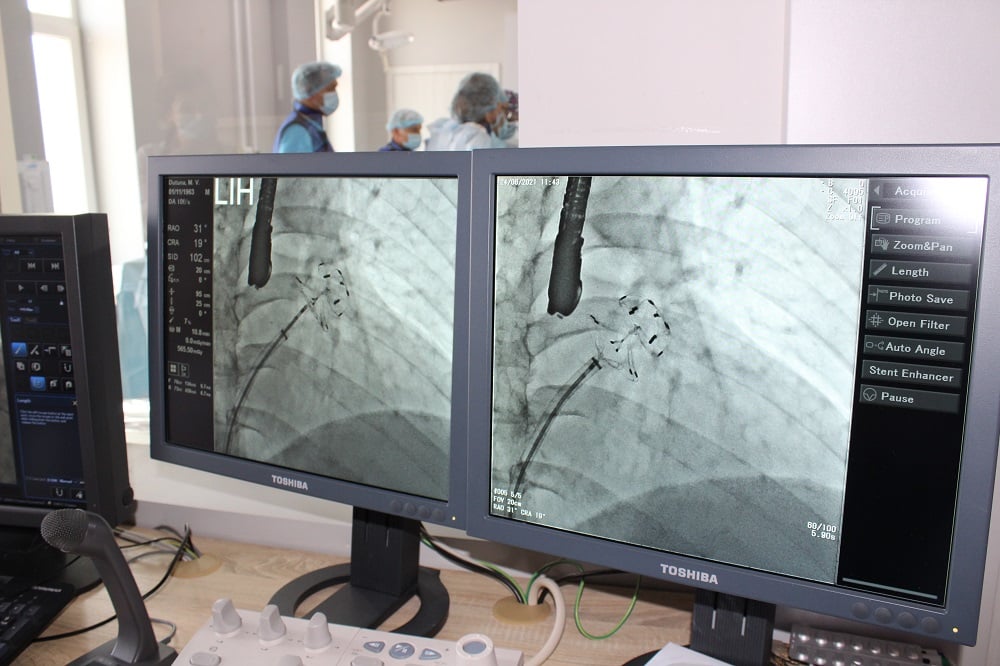

Пацієнтам імплантовано спеціальний пристрій – оклюдер останнього покоління UltraSept LAA виробництва CARDIA (USA).

Обидві операції пройшли успішно. Вони проводилися за допомогою ангіографа (із застосуванням рентгенологічного обладнання) через прокол у судині на нозі і не потребували хірургічних розрізів.